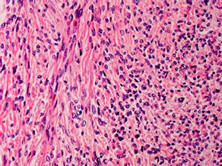

卵巢纤维瘤

卵巢纤维瘤是卵巢索间质肿瘤中常见的良性肿瘤。常伴有腹水,偶有胸积液,是其特征性表...